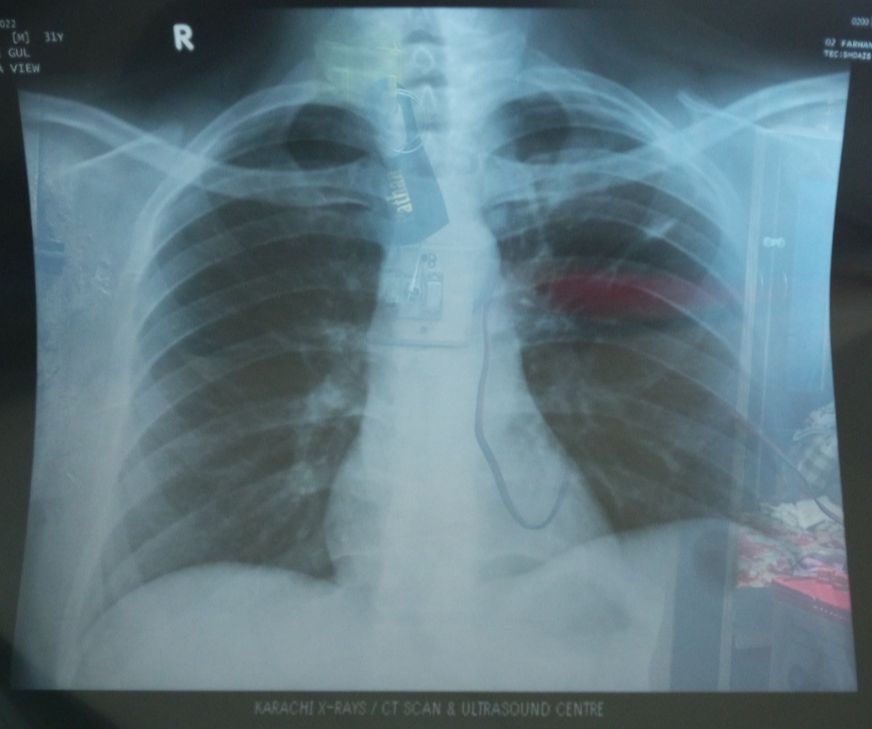

میں نے ایکسرے کرواۓ تو میرے چیسٹ پر داغ کے نشانات واضح ہوۓہیں اس نشانات کو ختم کرنے کیلۓ کونسے ڈاکٹر کے پاس جانا چاہیۓ؟؟؟

kindly share the picture of your chest xray

Check it out

X-ray report